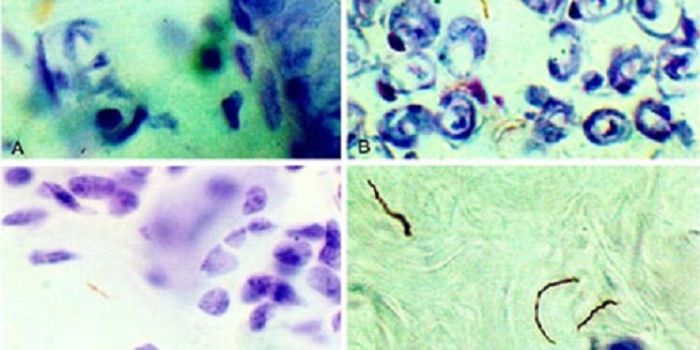

APR 16, 2015ImmunologyAbout 15% of patients with Lyme disease develop peripheral and central nervous system involvement, often accompanied by ...

AUG 25, 2016MicrobiologyResearchers have learned more about how Lyme disease invades the body, and will publish their findings September 6 in Ce ...